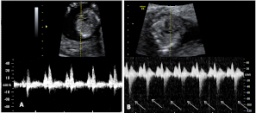

Ecografía de la semana 12

Confirma la edad gestacional y el número de bebés

Los motivos por los que los ginecólogos recomiendan realizar una ecografía en la semana 12 de embarazo tienen que ver con el desarrollo anatómico y el tamaño del feto: ahora es lo bastante grande para comprobar si presenta anomalías. Además, ya se puede ver con claridad si hay uno o dos (o tres) bebés, calcular  la fecha probable de parto teniendo en cuenta la edad gestacional, y confirmar que esta coincide con el desarrollo del bebé. Se puede medir el llamado pliegue nucal (si sobrepasa unos parámetros a veces es indicio de problemas cromosómicos) y, si el bebé se deja, conocer su sexo.